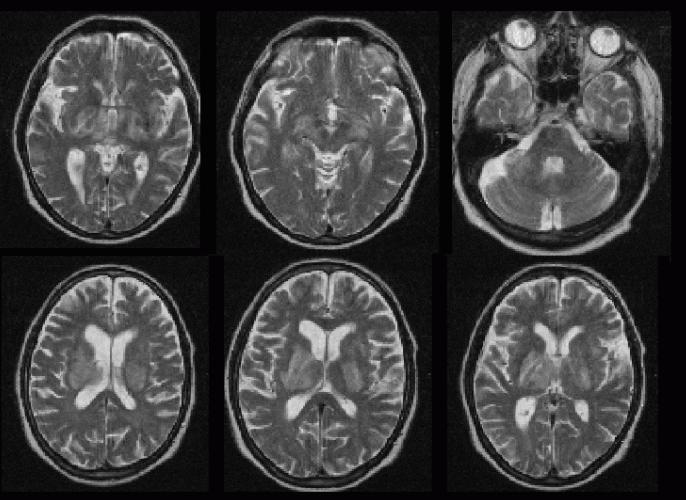

Формы токсоплазмоза. Осложнения

Сначала рассмотрим подробнее, к чему приводит запущенный токсоплазмоз. Симптомы у человека (фото на пленке посредством МРТ в разрезе) осложненного течения болезни в виде образований в мозговых оболочках просматриваются на нижеприведенном рисунке. Зона поражения обозначена красным квадратом, и она свидетельствует о развитии гнойного менингоэнцефалита. Этому состоянию могут сопутствовать осложнения — слепота, истощение, паралич. Смерть наступает от обширного и стремительно развивающегося поражения головного мозга.

Следует отметить, что токсоплазмоз мозга (симптомы и морфологические признаки) проявляется весьма разнообразно. Если проводить микроскопическое исследование, то наиболее характерными будут рассеянные по головному и спинному мозгу гранулемы, которые состоят из больших эпителиоидных клеток, лимфоцитов. Гранулемы заключают в себе паразитов и окружены отеками с очагами некроза.